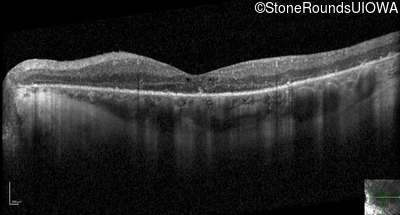

Optical Coherence Tomography - Right - 20/125 sc

Exemplar / OCT Stack